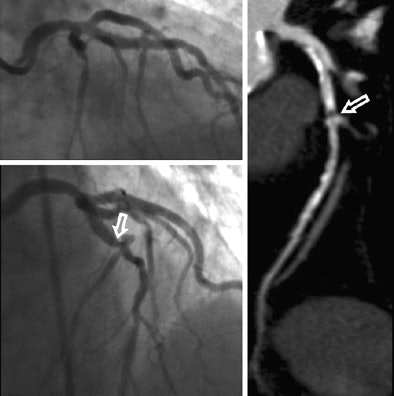

On the other hand, 11 stenoses ≥ 50% in 11 patients seen at coronary CTA were not seen at the initial reading of angiography findings. After unblinding of CT findings, six of these stenoses were subsequently confirmed at angiography.

For example, in one patient conventional angiography missed left main artery stenosis, Schoepf said. Left main lesions "are notoriously difficult to evaluate with catheter angiography," he said, and in that patient "the tip of the catheter was seated beyond the lesion, so if you inject contrast in a spot distal to the actual lesion you will miss it." Catheter placement is, of course, not an issue in CT where you're getting a 3D view of the anatomy.